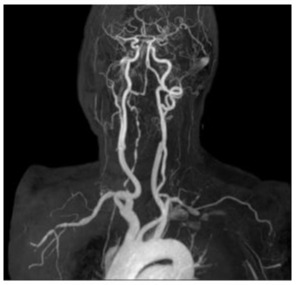

Angio-MRI with Dotarem® (meglumine gadoterate) showed strong acquisition of contrast on the walls of brachyocephalic trunk, both subclavian arteries and right vertebral artery. (Figure 1A, Figure 1B).

Figure 1A: Angio-MRI (21.3.2018) of the supraaortic vessels that shows irregularity of the right subclavian artery with subocclusion, irregular appearance of the right vertebral artery.